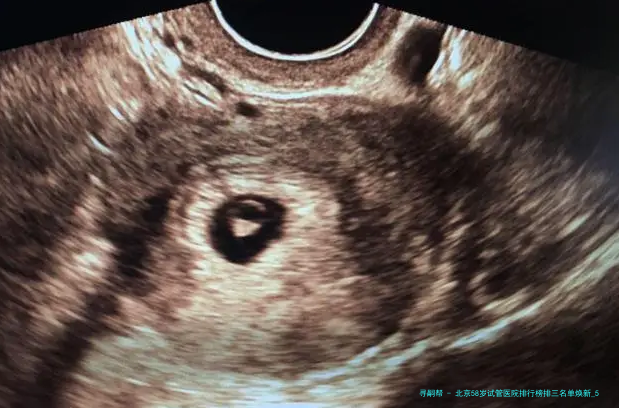

“医生,我58岁AMH值几乎为零,仍旧有可能用自己的卵子做试管吗?”在北京某生殖中心咨询室,一位鬓脚花白的女士紧握化验单的手悄悄发抖——这便是很多超高龄家庭求子路的真实缩影💔。58岁生育堪称“逆天改命”🧬:卵巢功效彻底衰竭、胚胎染色体不同寻常率超80、妊娠并发症风险迅猛上涨……选错医院不仅人财两空,更可能错失后的生育机会!2025年北京具备试管资质的医院达18家,但真实擅长超高龄方案的仅寥寥数家。本文结合新临床数据,揭晓严选前三医院排行、反转策略与性价比方案,让每一分盼望都用在刀刃上!